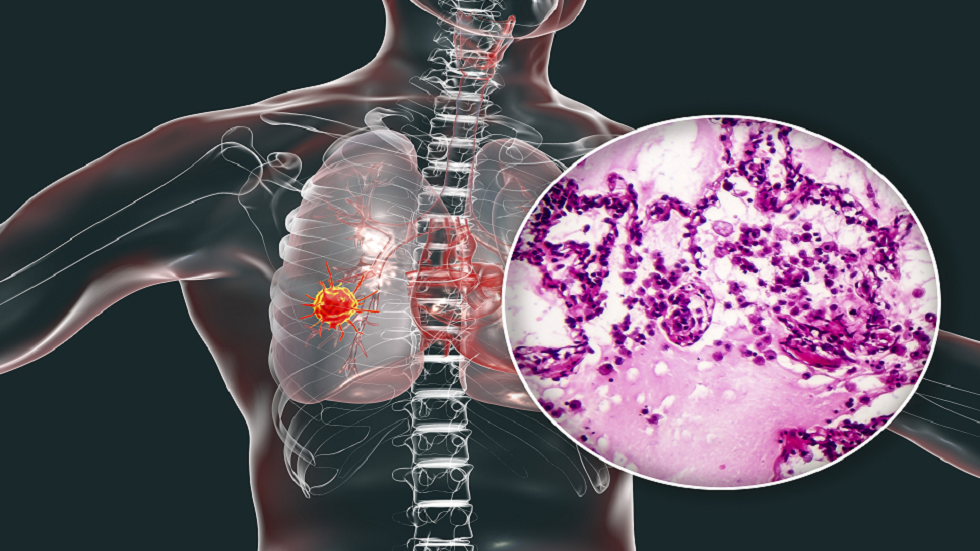

خمس "علامات وأعراض مفاجئة" يجب ألا نتجاهلها قد تدل على الإصابة بسرطان الرئة